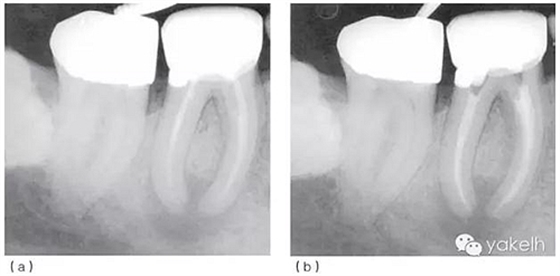

圖5.1.2(a)46根管再治療前X線片?,F(xiàn)有修復(fù)體、核及兩個(gè)不銹鋼樁均已安全拆除,患牙用不銹鋼帶環(huán)和Ketac-SilverTM臨時(shí)修復(fù),這為后續(xù)治療提供了無微滲漏且穩(wěn)定的局部環(huán)境。(b)46根管再治療后X線片。與圖5.1.1相比,根管預(yù)備和充填更接近理想的工作長(zhǎng)度,致密度更高。